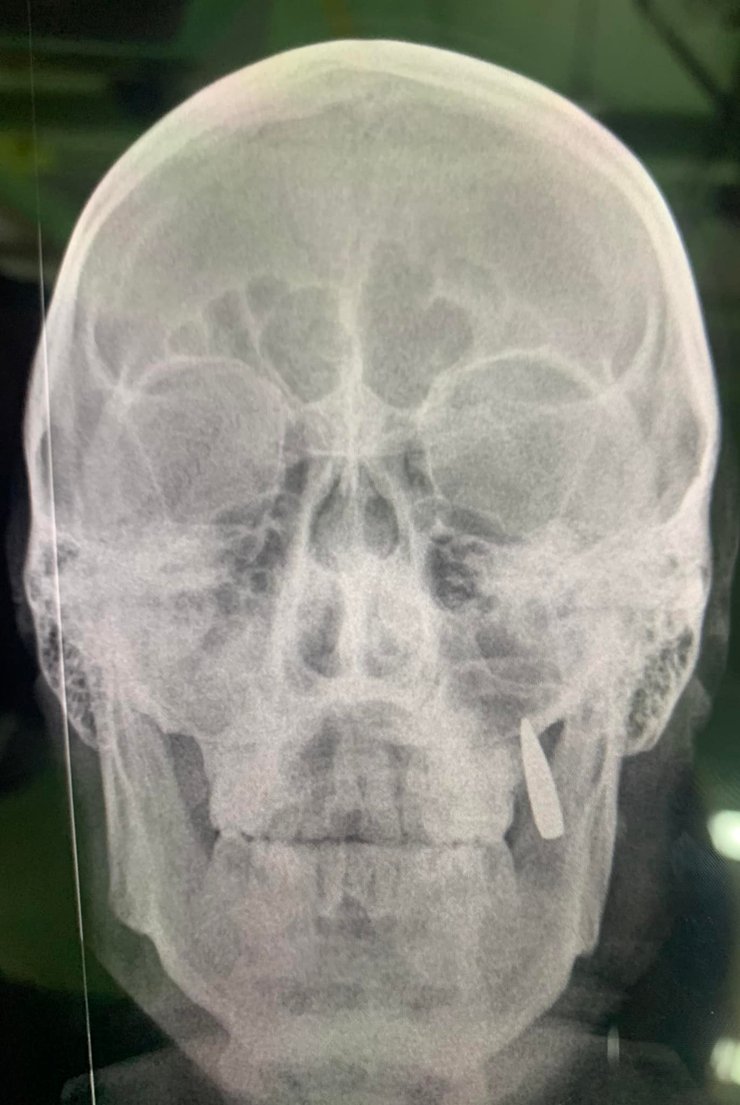

"Робимо рентген: замість двох зубів, в щелепі застрягла куля. Ну так собі імплант", — зазначила Корчинська.

Рентген (куля в щелепі військового)

Фото: Фейсбук Оксани Корчинської